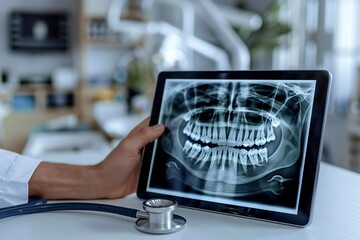

Definitely. One of the perks of our office is that we provide both pediatric dentistry and orthodontics. Dr. Beanca Chu and our orthodontist, Dr. Shawn Yu, use digital X-rays to track exactly how the permanent teeth are moving into place.

A panoramic X-ray (the one that rotates around the head) gives us a full "map" of the jaws. It helps us see if the jaw is aligned correctly or if there’s enough room for adult teeth to erupt. The American Association of Orthodontists recommends an evaluation by age 7, and having these X-rays on file allows us to catch bite issues early, often shortening the time your child might eventually need to spend in braces or clear aligners.